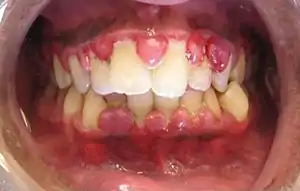

Gingivitis, a common cause of inflammatory gingival enlargement. | |